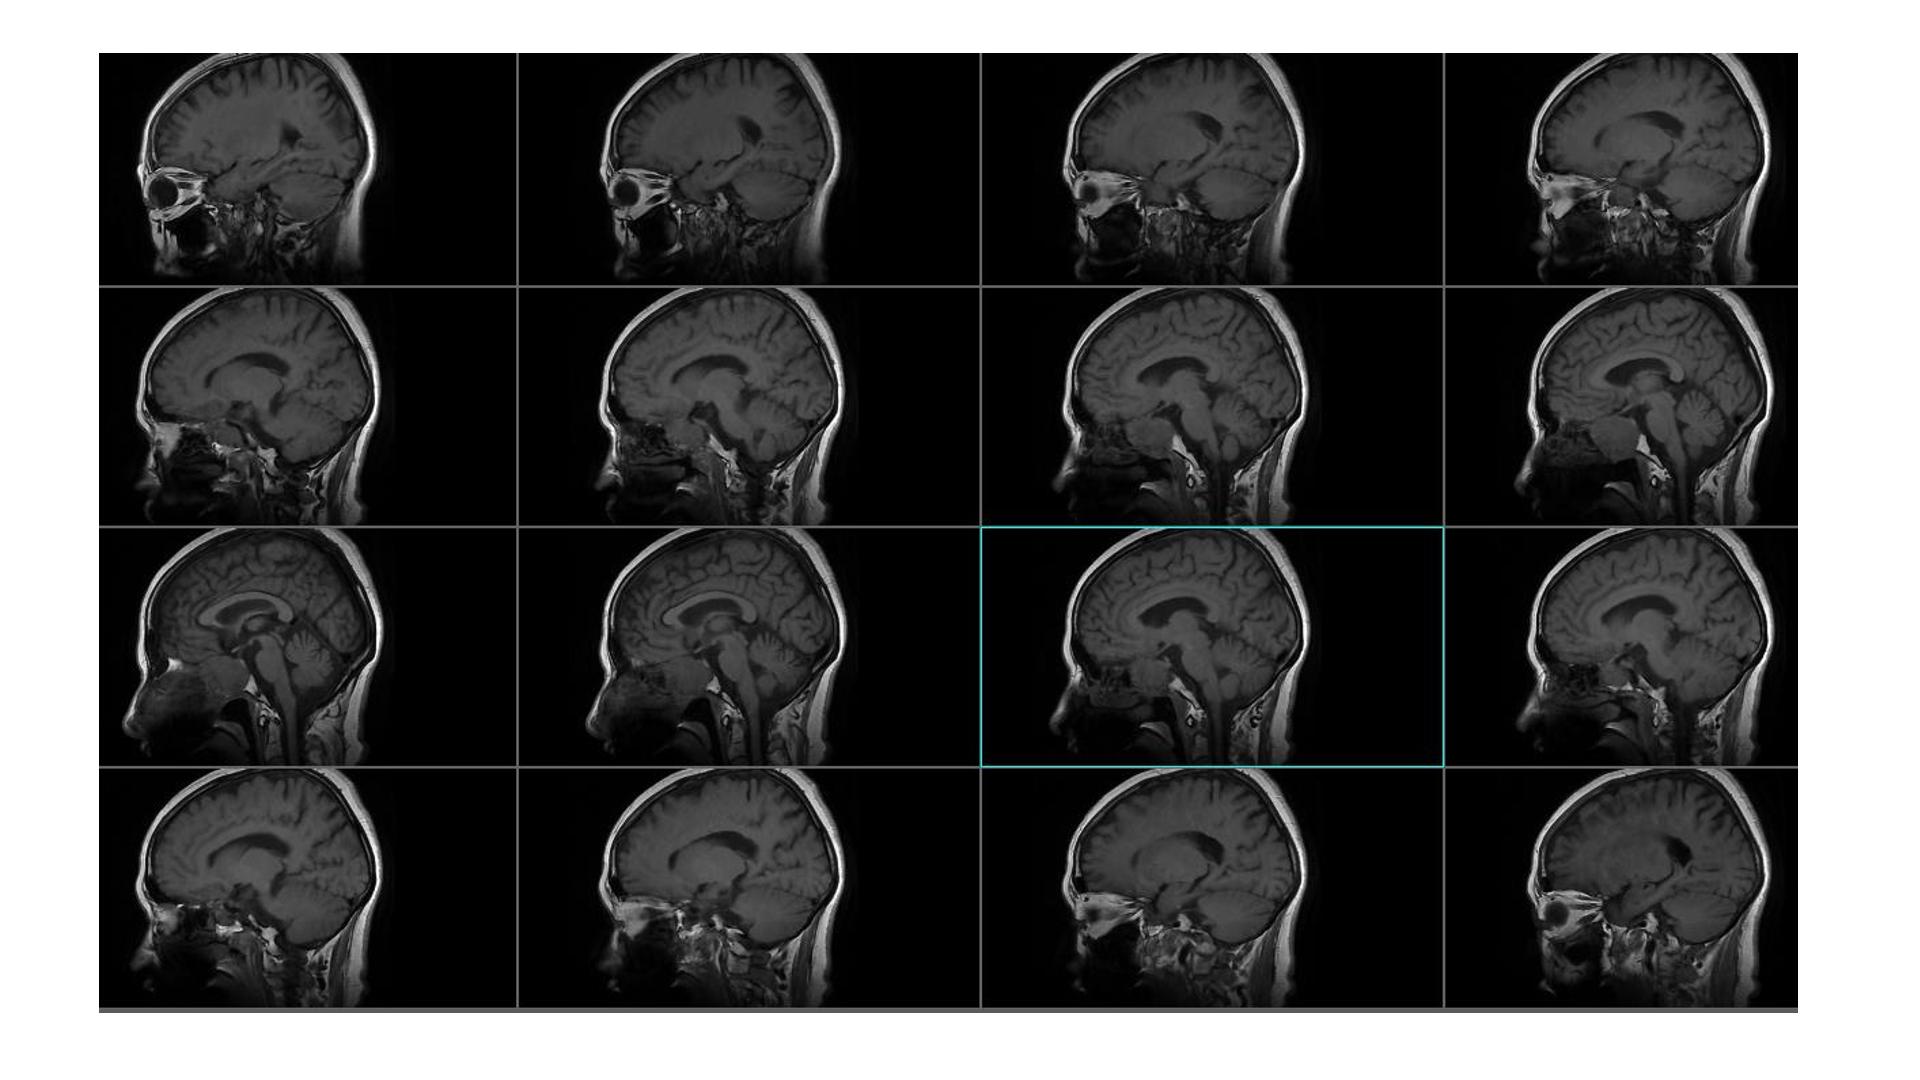

鞍区占位,蝶鞍扩大明显,侵袭海绵窦。